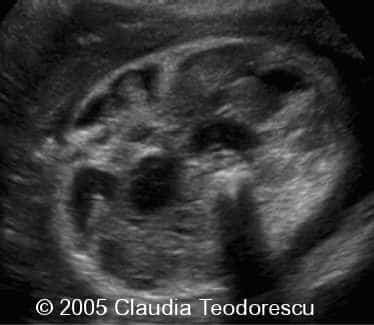

Case report: This is a woman 35-year-old , G2 P0 . She had several unremarkable ultrasound examinations during the entire pregnancy prior to 30 weeks of gestation. The following images were done at 30 weeks. The rest of the female fetus was normal, as well as the left arm ( last image ).

Images of the right arm: